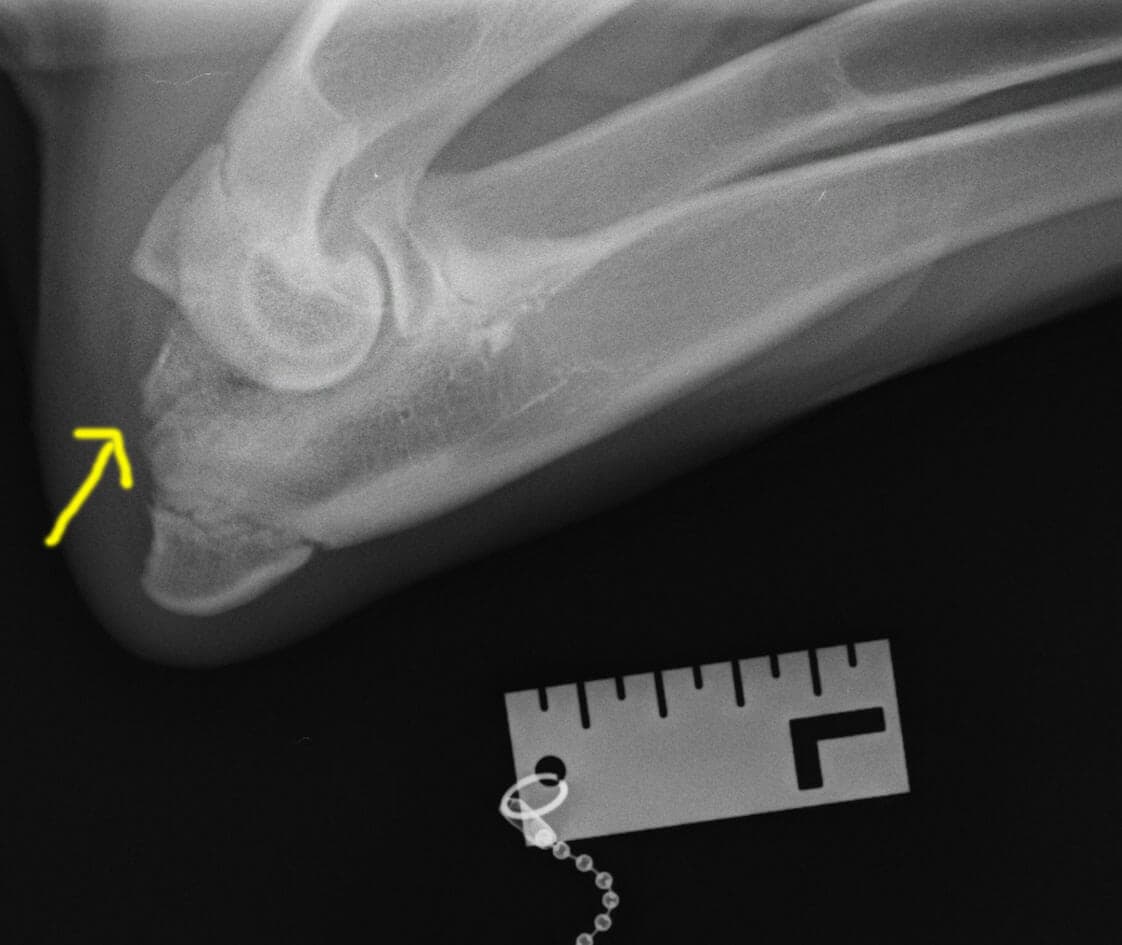

Кане-корсо 5 месяцев. Диагноз: фрагментация крючковидного отростка.

Рекомендована операция ДДОЛ.

Операция ПБОЛ в возрасте 6.5 мес. Красная стрелка: зона распила;

желтая стрелка: практически лизированный крючковидный отросток.